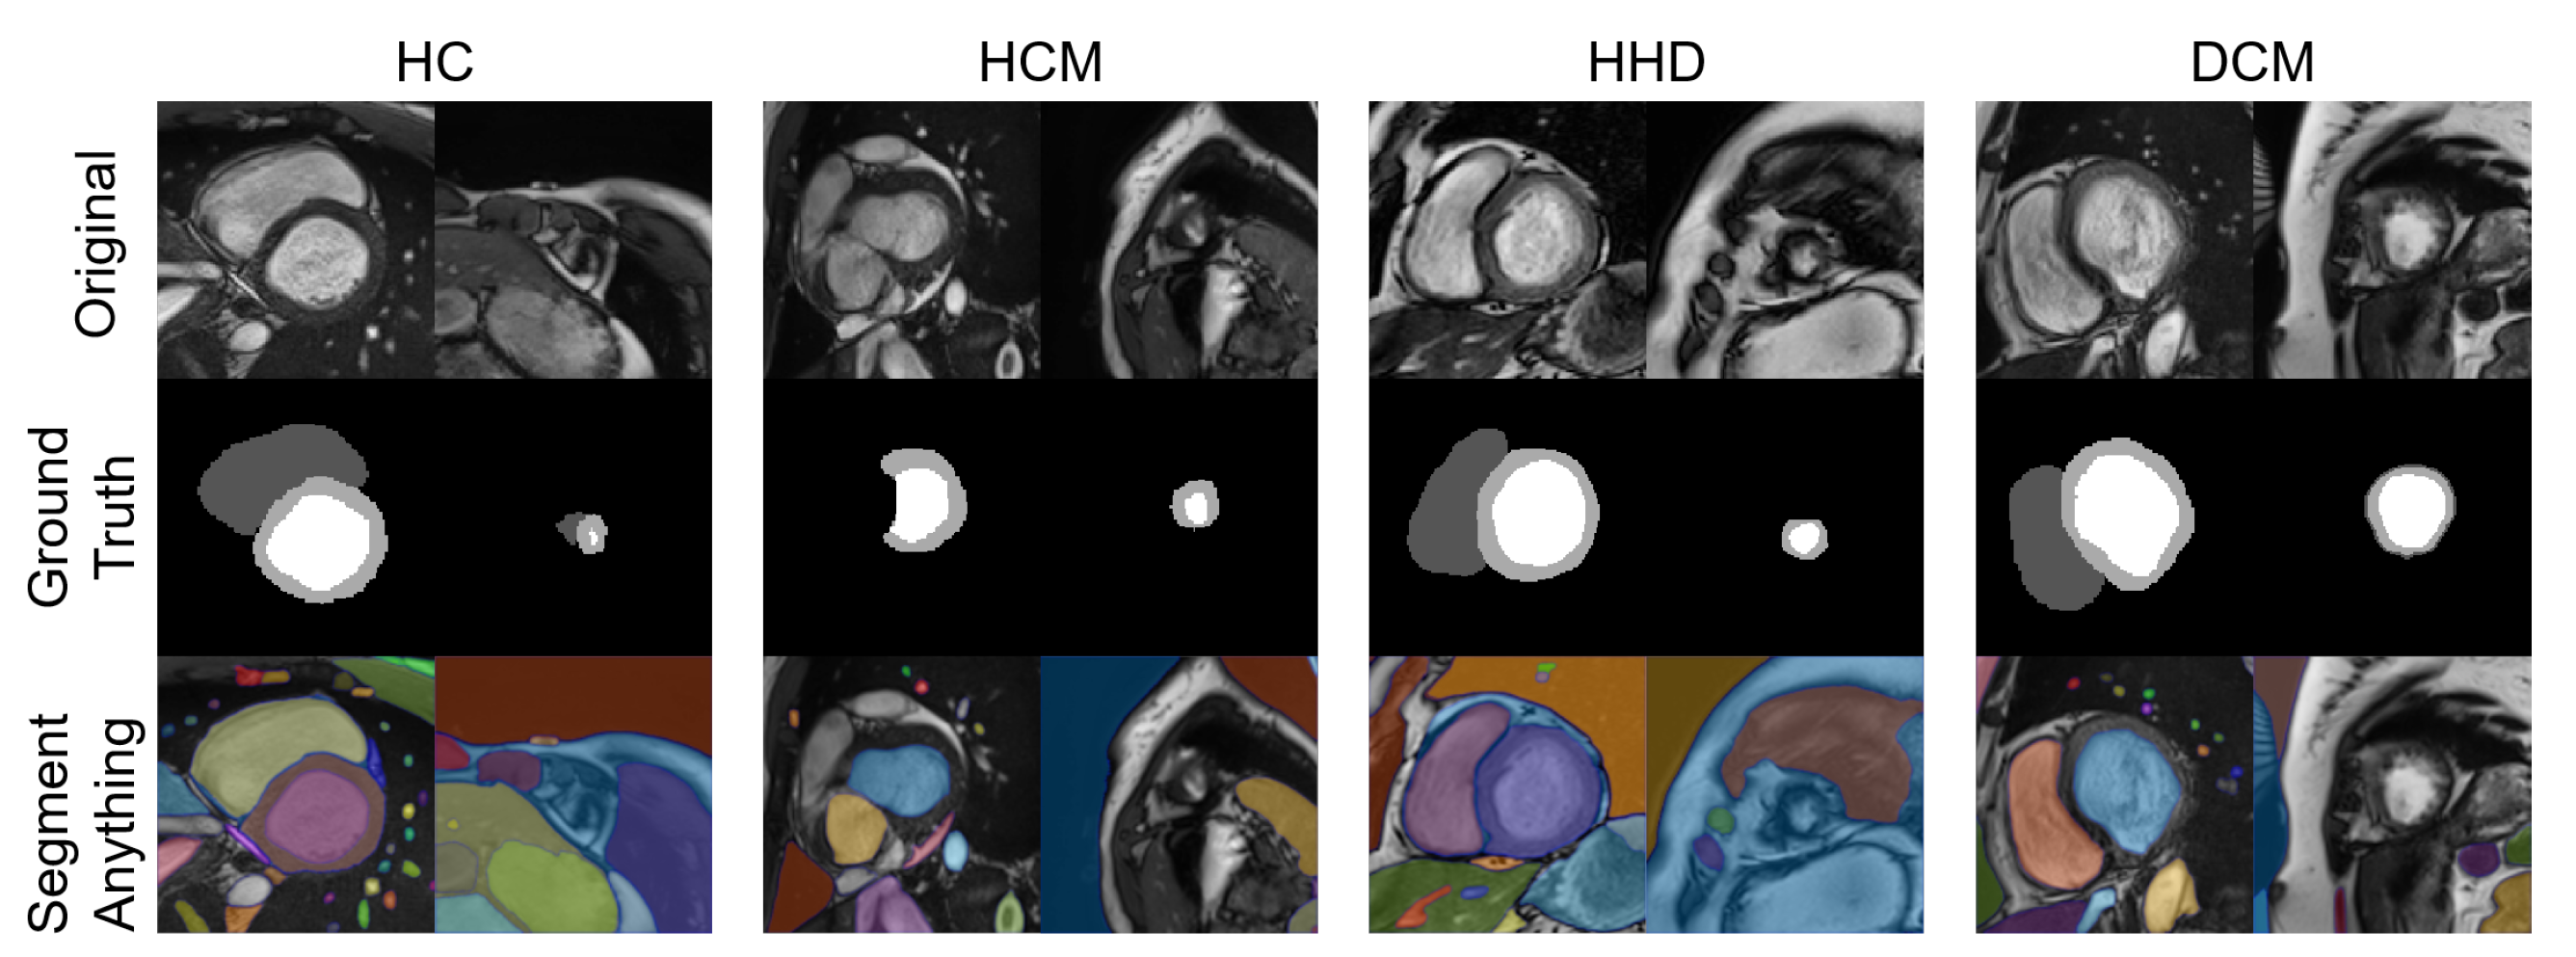

A total of eight images were tested with the SAM “every” mode. The segmentation results are shown together with the manual segmentations in Figure 10. The results of the SAM showed an acceptable performance on the basal slices; however, for the apical slices, none of the four apical slices showed acceptable results.

Figure 10. Eight images with manual segmentations and SAM segmentations. For each disease type, we selected an apical slice and a basal slice.

With the advent of the segment anything model (SAM) [31], we chose some of our images as inputs and tested their segmentation ability with the “every” mode https://segment-anything.com/demo (accessed on 10 April 2023).

4.3. QC with the Mature Segmentation Model

In contrast to diagnostic applications, a QC system should prioritize the detection of bad-quality segmentations, rather than improving the classification accuracy. As a result, we chose the NDR as our primary criterion for the classification evaluation. Additionally, we observed that deep learning segmentation models for cardiac segmentation are currently well-developed. The reported average DSC is 0.85–0.97 for the ACDC-2017 dataset and M&M challenge dataset with various DL model structures [3,33,34,35]. As previously mentioned, mal-segmentations at the slice level are primarily distributed in the apical or basal regions of the heart. However, these low-quality segmentations have little effect on the 3D DSC prediction. This partially explains why the 3D DSC is higher than the 2D DSC (refer to Table 4). However, it is important to note that the absence of apical or basal slice segmentations can significantly impact the 3D radiomics features, such as the maximal long axis length, particularly in the shape feature group. This phenomenon was also observed in our experiment (Supplementary Tables S7 and S8). Meanwhile, although coarse borders may not significantly impact the 2D or 3D DSC, certain radiomics features are sensitive to edges, as demonstrated in previous studies [36,37,38]. The characteristics exhibited by radiomics-based quality control systems provide a new evaluation perspective compared to previous methods. This makes radiomics an ideal method for automatic segmentation evaluation and quality control. As shown in Figure 10, the segmentation of apical slices remains challenging, which is why a quality control system is necessary, even with the use of large models, such as SAM.